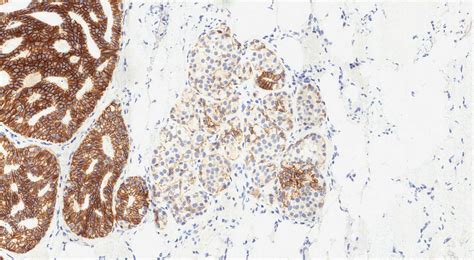

When those cells not only multiply but also begin to look and behave differently than normal cells—yet are not considered cancer—it is classified as “atypical.” Therefore, ADH represents a state of overgrowth where the cells lining the breast ducts have acquired some features of cancer but remain confined within the ductal structure. It is essentially a marker that indicates your breast cells are prone to genetic changes that could lead to breast cancer in the future.

• Chemoprevention: Medications like Tamoxifen or Raloxifene may be discussed to reduce the risk of future breast cancer development by blocking estrogen receptors.